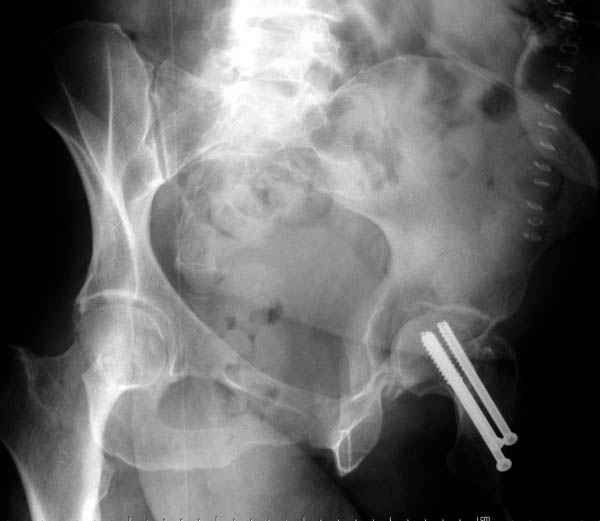

Мы сейчас наблюдаем больную с похожим состоянием, больной 54, после автоаварии, со множественными

переломами скелета.

Состояние осложнена черепномозговой и абдоминальной травмой, переломы L2-5, челюстно-лицевые переломы и состояние после транспланта почки.

Удаление селезенки при поступлении, была нестабильная, в данное время приходит в сознании, находилась в реанимации, перевели в общую палату.

Перелом шейки смогли зафиксировать через пару дней, ацетабулум до сих пор не оперирован, на вытяжении.

Из-за упущенного времени (три недели с момента

поступления) ацетабулум ведем консервативно.

Фиксацию шейки провели когда получили окно, быстро

перкутанно смогли провести шурупы.